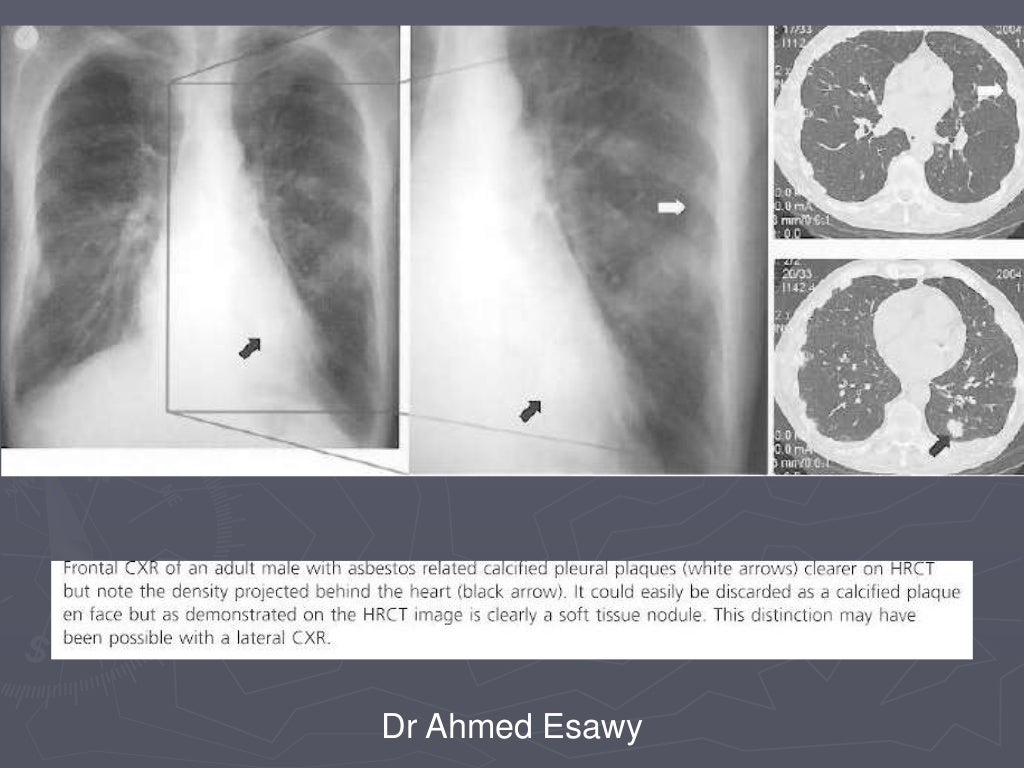

Linear lung density x ray Dr Ahmed Esawy

Linear lung density x ray Dr Ahmed Esawy What Is A Linear Density In The Lungs Lung densitometry, namely measurement of lung density, is based on the. These areas show increased density inside the lungs which could indicate. When it comes to any lung density, unfortunately, usually the first thought that creeps into the doctor's head is going to be some type of lung. In chest radiology, reticular and linear opacification refers to a broad subgroup. What Is A Linear Density In The Lungs.